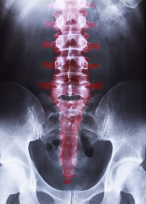

허리 척추협착증 증상 원인 치료방법 등 허리 척추 협착증에 관한 정보를 정리해드리도록 하겠습니다.허리 척추협착증은 허리 부근 척추 채널이 좁아져서 척추 신경이 압박을 받아 발생하는 질환입니다. 척추 채널이 좁아지는 원인으로는 나이, 척추 골절, 디스크 병변, 척추 관절염 등이 있습니다. 허리 척추협착증의 증상으로는 허리통증, 무릎 아래 쪽 발의 저림, 마비 등이 있으며, 증상이 심한 경우에는 수술이 필요할 수 있습니다. 허리 척추협착증은 대개 노인층에서 많이 발생하지만, 현대 사회에서는 장시간의 앉은 자세나 비만, 부적절한 운동 등으로 인해 젊은 층에서도 발생할 가능성이 있습니다. 따라서, 척추 건강을 유지하기 위해 규칙적인 운동, 올바른 자세 유지, 척추 근육 강화 등이 필요합니다.

허리 척추협착증은 허리 부근 척추 채널이 좁아져서 척추 신경이 압박을 받아 발생하는 질환입니다. 척추 채널이 좁아지는 원인으로는 나이, 척추 골절, 디스크 병변, 척추 관절염 등이 있습니다. 허리 척추협착증의 주요 증상은 허리통증입니다. 일반적으로 허리 통증은 좁아진 척추 채널에서 발생하는 신경통으로 인한 것입니다. 이 통증은 다리와 발, 허리 주변 부위까지 퍼질 수 있습니다.

또한, 허리 척추협착증은 하지의 압박성 신경증상을 유발할 수 있습니다. 다리나 발의 저림, 마비, 근력 약화 등이 대표적인 증상입니다. 이러한 증상은 척추 신경이 충분한 공간을 갖지 못해 생기는 문제로, 신경을 제거하거나 압박을 줄이는 치료를 통해 개선할 수 있습니다.

이 외에도, 척추 신경 압박으로 인해 복통, 어깨나 팔의 통증, 가끔은 손가락의 저림 등 다양한 증상이 나타날 수 있습니다. 하지만, 이러한 증상은 다른 질환이나 소견에 따라 발생할 수도 있기 때문에 정확한 진단을 위해 전문가의 진료를 받아야 합니다.